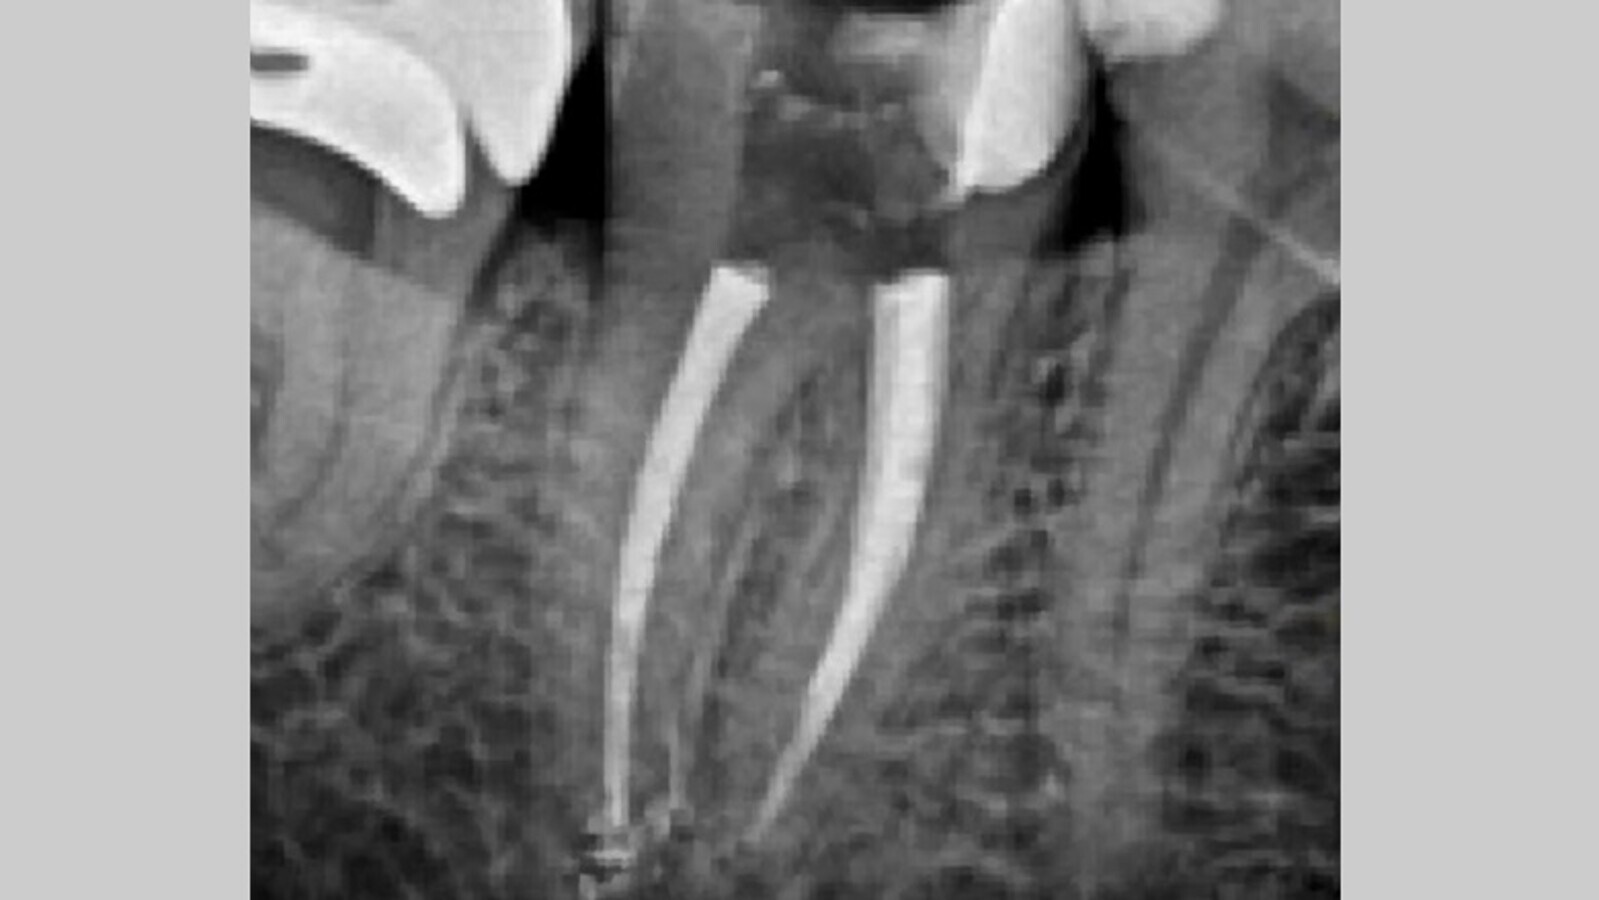

La configuración de los conductos mesiales resulta en la unión en el tercio apical, compartiendo el mismo foramen. Una vez se permeabilizan los conductos con la lima del 10 K- files, se realiza un glide path hasta alcanzar con una lima 15 k file (Denstply) la longitud de trabajo. Es en ese momento se toma una radiografía de comprobación de la longitud de trabajo actual (Fig. 3), y tras confirmar que la longitud es correcta, procedemos a realizar la instrumentación mecánica, en este caso reciprocante con el sistema Reciproc Blue (VDW Dental) que consta de varias limas reciprocantes para la limpieza y conformación de los conductos. Utilizamos este sistema en el motor Endoradar (Woodpecker) el cual viene equipado con localizador electrónico de ápices incorporado. Para la conformación final de los conductos a nivel apical se utiliza el sistema ProFile (Denstply), concretamente la lima ProFile 35.04 en conductos mesiales y la lima 40.04 en el conducto distal. Durante toda la instrumentación irrigamos con NaOCl al 4,25%. Realizamos el protocolo final de activación con activador sónico, tres ciclos: NaOCl 4,25% - EDTA 17% - NaOCl 4,25%. Secamos los conductos con puntas de papel calibradas a los calibres finales de cada conducto (Denstply).

Fig. 3. Radiografía de conductometría. Localización de dos conductos mesiales y un conducto distal.